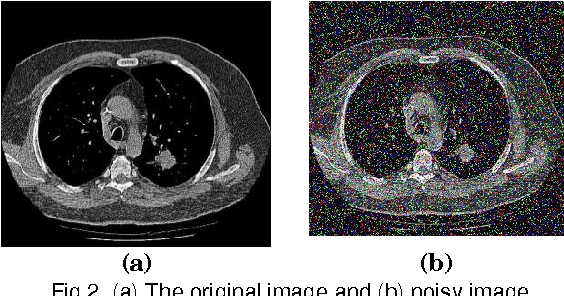

Abstract:Lung cancer is the deadliest type of cancer for both men and women. Feature selection plays a vital role in cancer classification. This paper investigates the feature selection process in Computed Tomographic (CT) lung cancer images using soft set theory. We propose a new soft set based unsupervised feature selection algorithm. Nineteen features are extracted from the segmented lung images using gray level co-occurence matrix (GLCM) and gray level different matrix (GLDM). In this paper, an efficient Unsupervised Soft Set based Quick Reduct (SSUSQR) algorithm is presented. This method is used to select features from the data set and compared with existing rough set based unsupervised feature selection methods. Then K-Means and Self Organizing Map (SOM) clustering algorithms are used to cluster the data. The performance of the feature selection algorithms is evaluated based on performance of clustering techniques. The results show that the proposed method effectively removes redundant features.